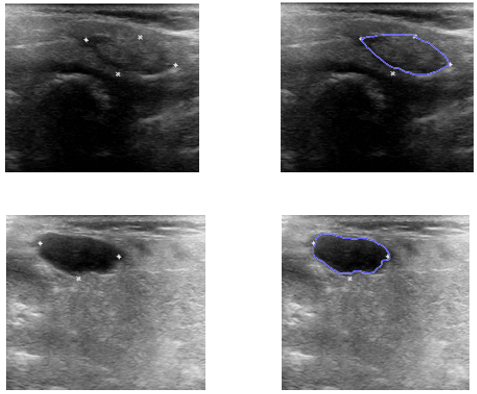

Machine learning (ML) techniques are becoming more commonplace as a result of their utility in addressing complex issues in several contexts. Using ML methods in ultrasonic imaging applications is nothing new, but there has been a meteoric rise in research into this area over the last several years. Medical diagnostics and non-destructive assessment use ultrasonic imaging extensively, and both have benefited from the use of machine learning methods. In the former, which constitutes the bulk of the review, solutions that pertain to the detection/classification of material defects or specific patterns are reported, while in the latter, studies were categorised according to the body organ examined and the methodology adopted. Finally, the study's analysis is summarised, and the key benefits of machine learning are explored..

D. Selvathi and V. S. Sharnitha, "Thyroid classification and segmentation in ultrasound images using machine learning algorithms," 2011 International Conference on Signal Processing, Communication, Computing and Networking Technologies, Thuckalay, India, 2011, pp. 836-841, doi: 10.1109/ICSCCN.2011.6024666.